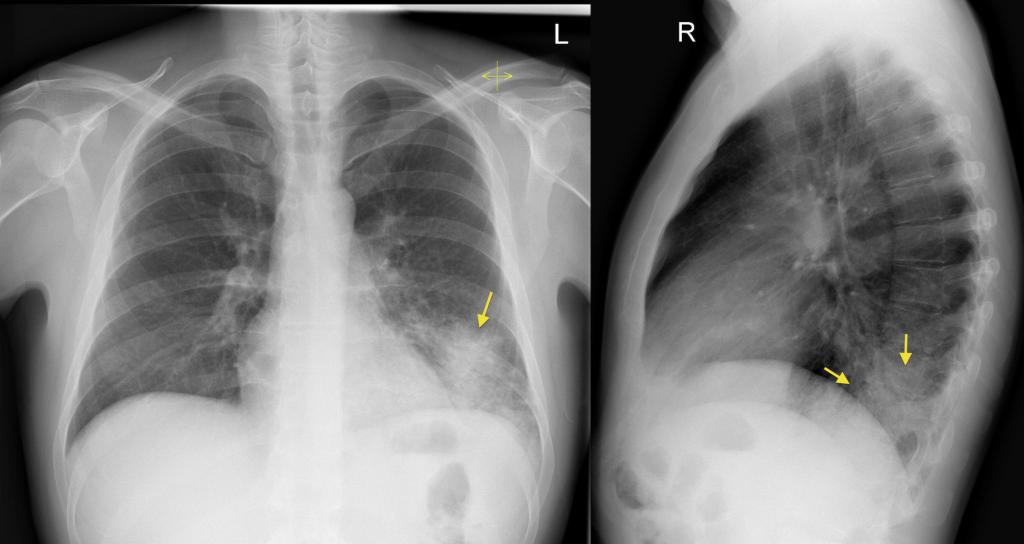

При атипичной пневмонии легких на рентгеновском снимке видны затемнения:

- мелкоочаговые – не более 3 мм;

- среднеочаговые – не более 7 мм;

- крупноочаговые – не более 12 мм;

- фокусные – более 12 мм.

Атипичная пневмония на рентгеновском снимке: